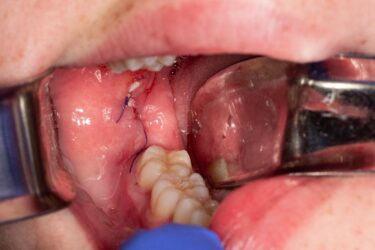

I have a case share. I have a patient who presented with Pericoronitis tooth number #1 and other impacted wisdom teeth. Medical history significant for von Willebrand‘s disease. I had a difficult time getting a medical status update from her PCP. Upon questioning the patient, it looks like a bleeding issues haven’t been too severe for her. However, I was concerned because my treatment plan included the removal of all four impacted wisdom teeth.

In this case, I modified my prescribing regiment to include 650 mg of transexamic acid in addition to analgesic medication. (Sig: instructed to take three times a day for up to four days.)

I had the patient take her first dose of transexamic acid with her oral sedatives one hour pre-op.

I was pleasantly surprised to observe the bleeding control we achieved immediately postop surgery referenced in the photos.